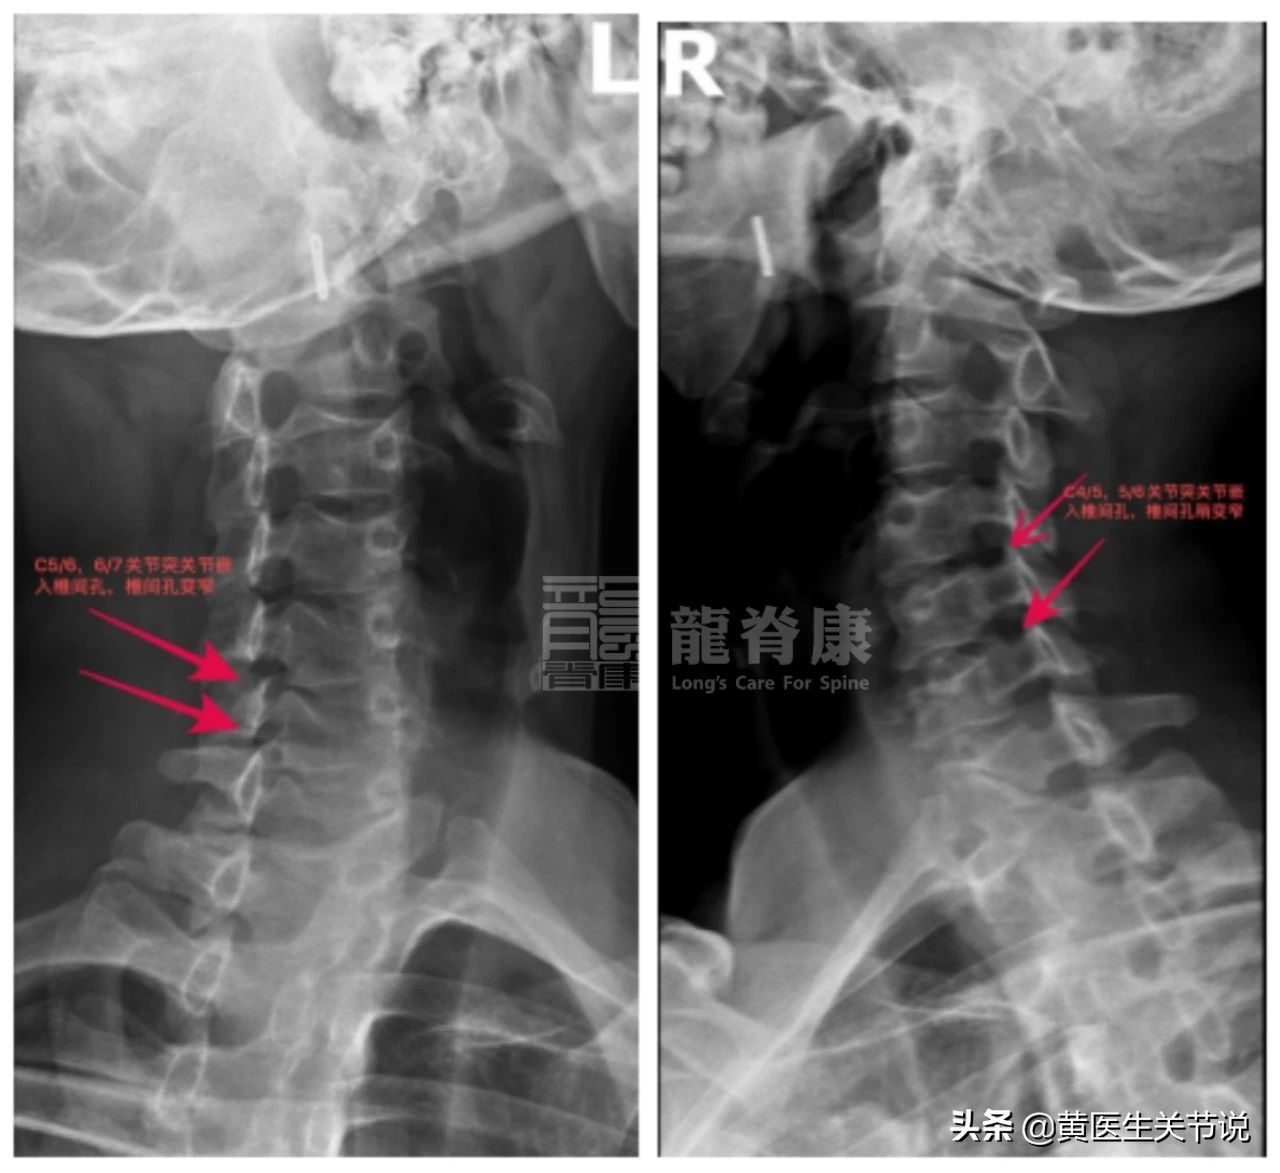

1、2020-4-2龙脊康阅片示:

颈椎生理曲度存,寰齿间距不等宽呈左窄右宽,前纵韧带及项韧带部少许钙化点,左侧C5/6、6/7椎间孔变窄,右侧C4/5、C5/6椎间孔稍变窄。

3、X光辅助检查: 2020-4-2龙脊康阅片示:颈椎生理曲度稍变直,寰齿间距左窄右宽,部分前纵韧带部分钙化,左侧C5/6.6/7,右侧C5/6椎间孔变窄。